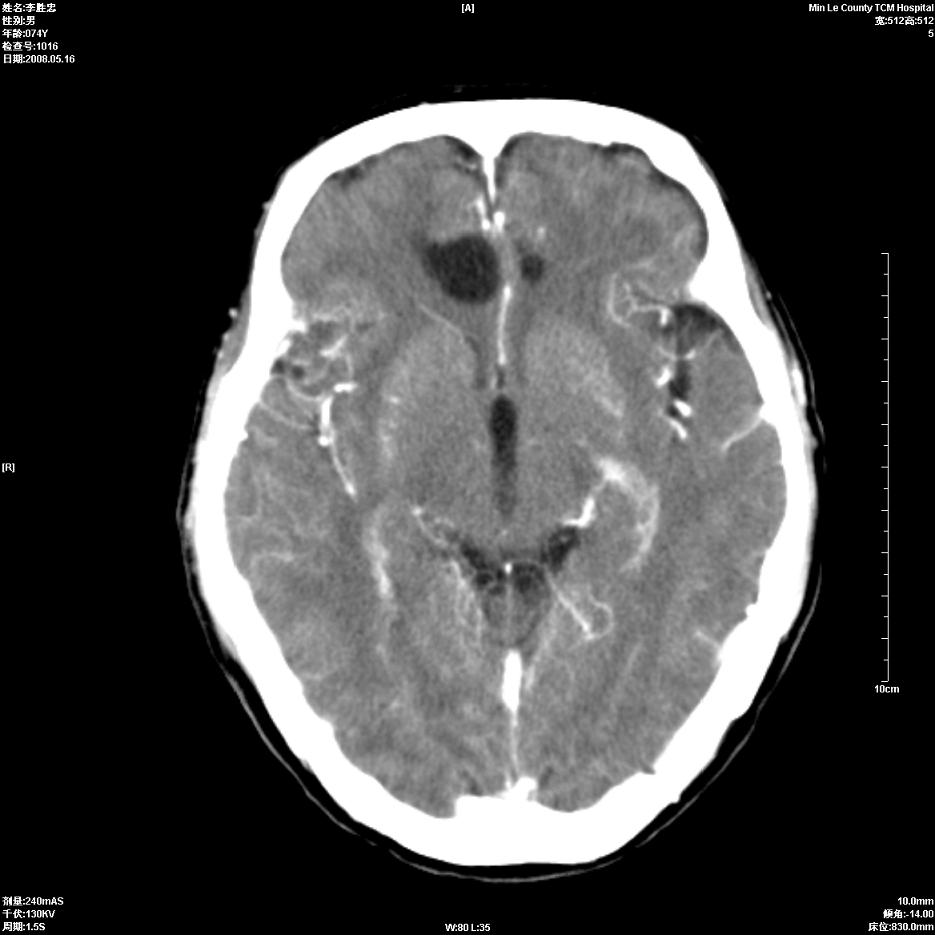

以下是引用hhcckk在2008-5-30 14:26:00的发言:[br]病灶跨中线,有占位效应,强化不明显,考虑胼胝体区低级别的星形细胞瘤可能性大,建议mr检查